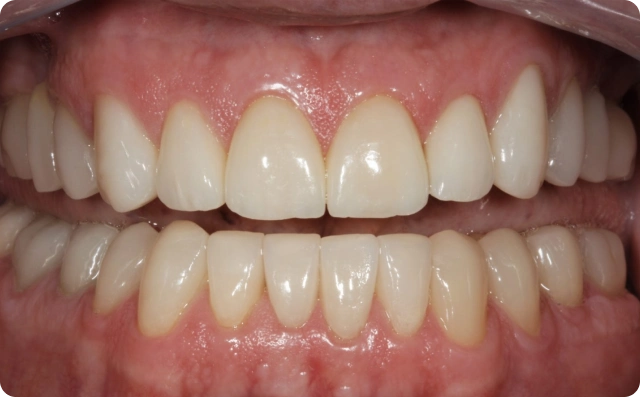

Antes

Depois

Foram confeccionadas facetas cerâmicas de dentes caninos a caninos superiores e inferiores, ponte fixa na região superior direita e coroas unitárias em dissilicato de lítio nos pré molares e molares.

Ao final do caso clínico, em 2017, indicamos uma placa miorrelaxante que foi confeccionada, no intuito de proteger os dentes de possíveis desgastes causados pela DTM (Distúrbio Temporo Mandibular).